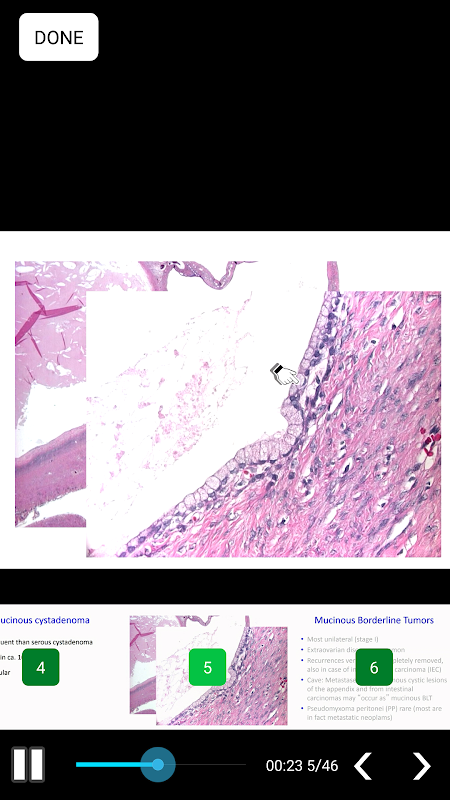

App ESAO eAcademy, aplikasi pembelajaran mudah alih rasmi dari European Society of Gynecological Oncology (ESGO), menawarkan akses kepada beribu-ribu bahan pendidikan dan aktiviti yang diterbitkan oleh ESGO selama bertahun-tahun seperti Program eLearning, Kuliah Terakreditasi, Penilaian Sendiri, Kuiz Belajar, Webinar, Webcast Asynchronous dan langsung, Teknik Video, Dokumen, Abstrak, Video pendapat pakar dan editorial dan banyak lagi ...